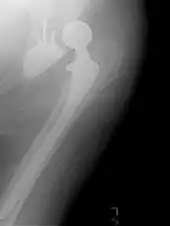

Dislocation

Dislocated artificial hip

Liner wear, particularly when over 2 mm, increases the risk of dislocation.[8] Liner creep, on the other hand, is normal remoulding.[9]

Dislocation (the ball coming out of the socket) is the most common complication. The most common causes vary by the duration since the surgery.